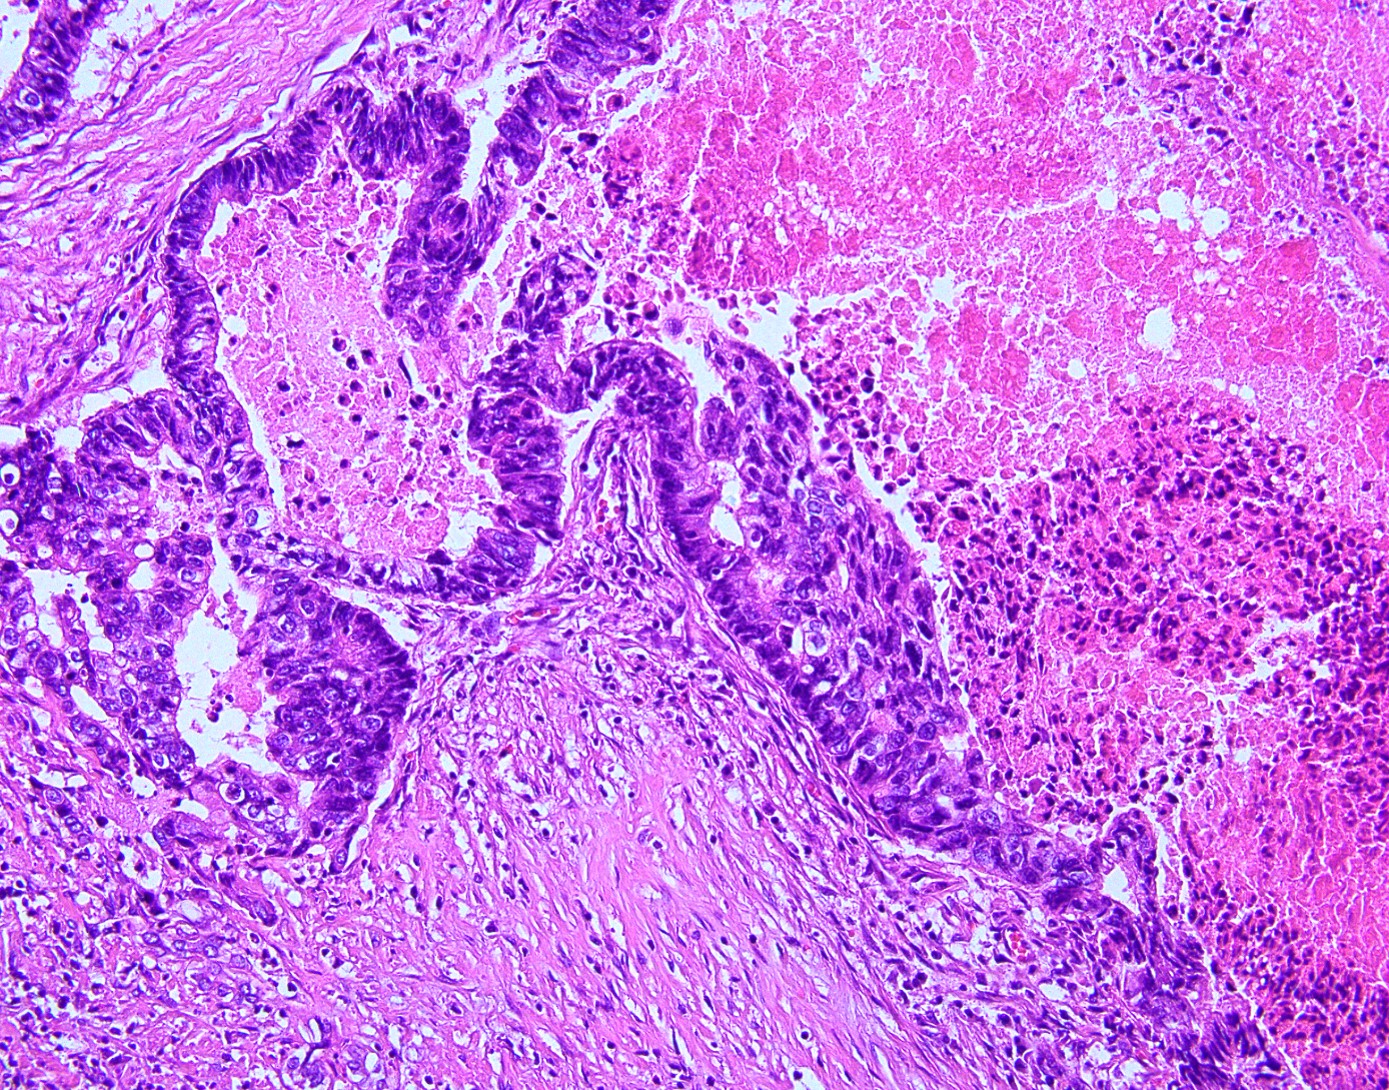

A 60-year-old woman was noted to have severe anemia and symptoms of colonic obstruction. Abdominal CT revealed a large lesion in a non-cirrhotic liver. Immunostains performed on a hepatic biopsy specimen revealed lesional cells to be positive for CK20 and CDX2 and negative for CK7, glypican-3, and TTF-1.

Answer: A.) Metastatic colonic adenocarcinoma